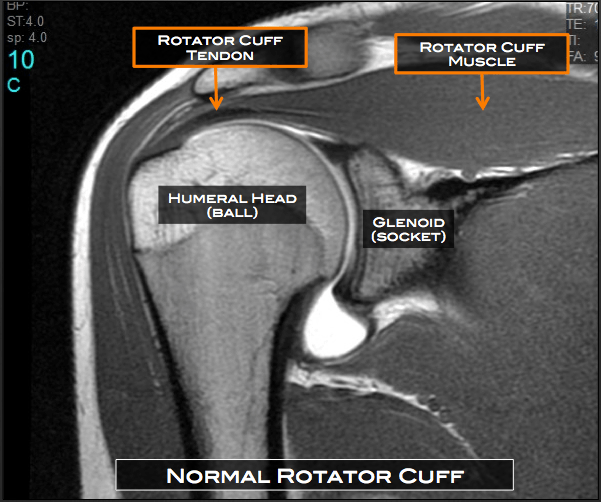

MRI Shoulder – Musculoskeletal Imaging

MRI AP shoulder. Unidad Especializada en Ortopedia y Traumatologia en …